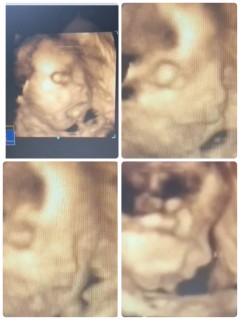

初めての4Dエコー☆ほとんど寝てましたが、お腹を押して起こすと機嫌悪そうに両足で顔面掻いてました笑 パパにもママにも似てるので、産まれてくるのが楽しみです♪